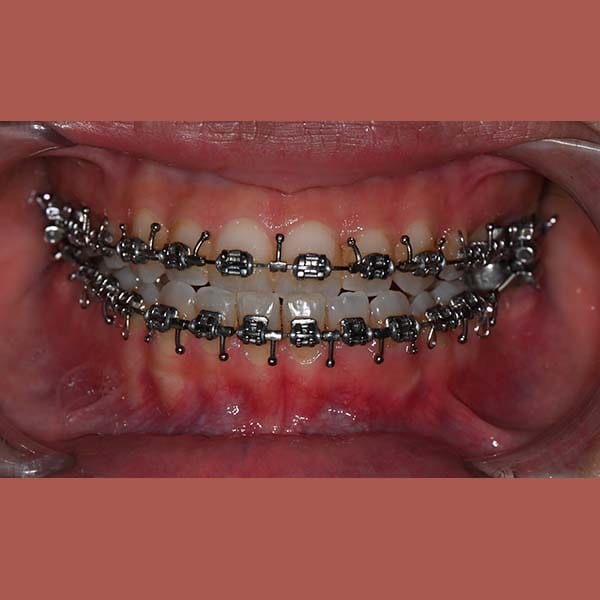

عانت هذه الشابة من بروز واضح في الذقن ناتج عن تقدم الفك السفلي، مما أثر على تناسق وجهها وسبب لها عضة معكوسة أمامية.

كما تظهر الصور، كانت النتيجة تحولاً كاملاً. تم استعادة الشكل الطبيعي للذقن والفك السفلي، وتم تصحيح العضة المعكوسة. في النهاية، أصبح بإمكان مراجعتنا الشابة أن تستمتع بابتسامة مميزة وواثقة وملامح وجه متناغمة.